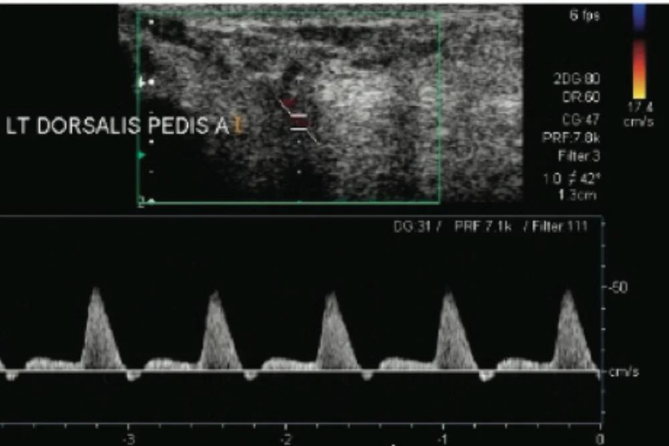

Peripheral Vascular Doppler

Enhance your expertise in vascular assessment. Improve diagnosis & treatment of peripheral vascular diseases.